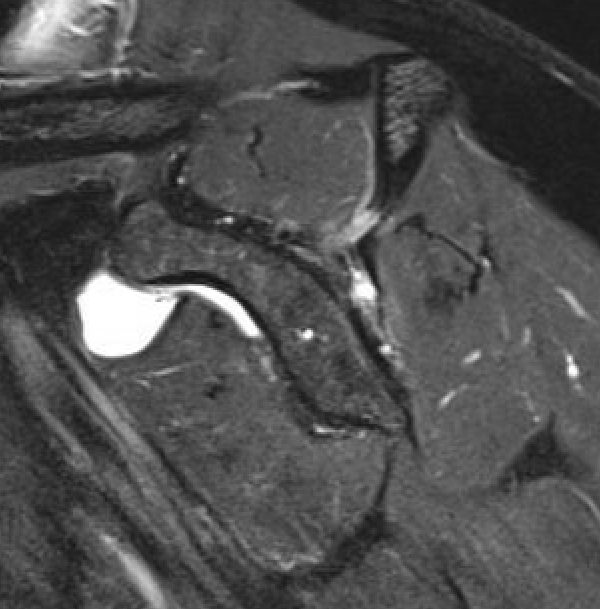

Goutallier classification

Amount of fatty degeneration in rotator cuff muscle belly on a T1 sagittal MRI

- systematic review of Goutallier grade and retear rates

- retear rates after surgical repair increase as the Goutallier stage increases

| Stage 3 | Stage 4 |

|---|---|

|

Equal fat and muscle MRI demonstrates grade 3 supraspinatus and infraspinatus |

More fat than muscle MRI demonstrates grade 4 infraspinatus |